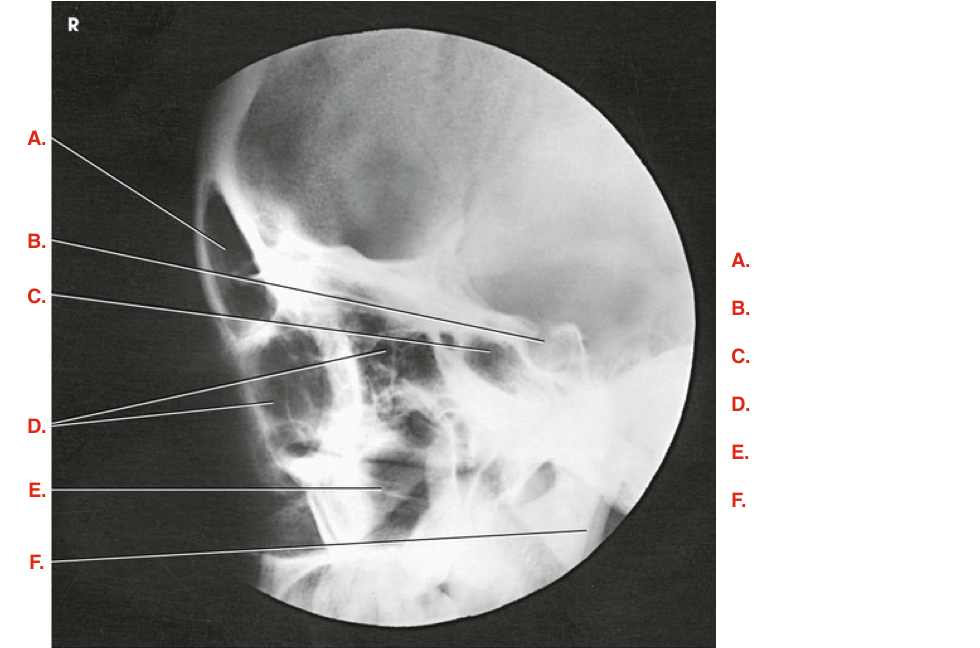

Question

Label the image

Image:

b7704515-7c01-4643-b5b1-a52a5f3729b5 (image/png)

Answer

frontal sinus

sella turcica

sphenoidal sinus

ethmoidal sinuses

maxillary sinus

superimposed mandibular rami